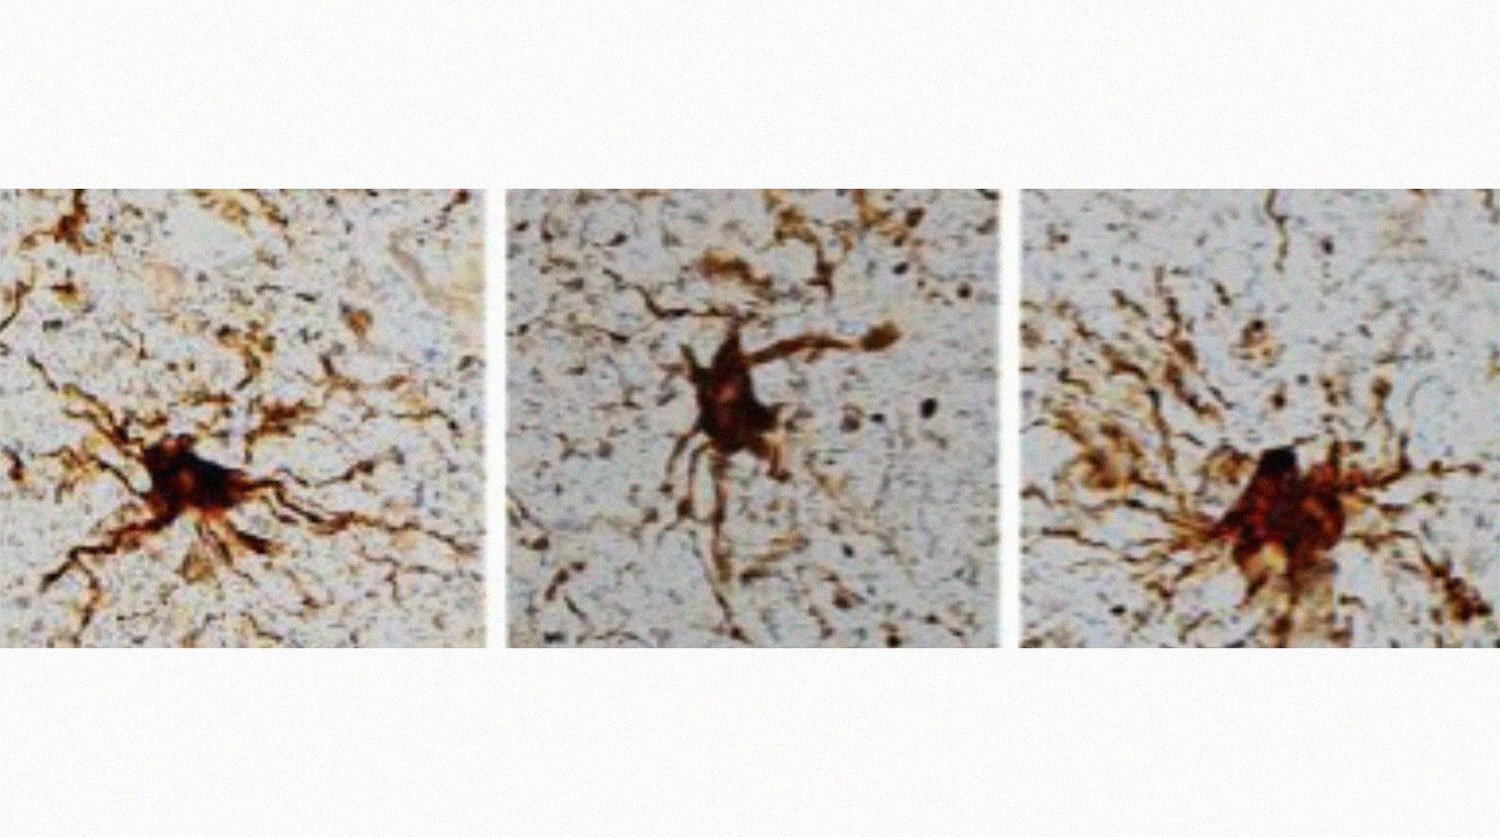

Они оказались специфичны для нейроглии — вспомогательных клеток нервной ткани. В мозге глиальных клеток примерно столько же, сколько нейронов. Они выполняют опорную, трофическую, секреторную, разграничительную, защитную функции, функцию обучения нейронов, играют важную роль в процессах памяти.

Оказалось, глиальные клетки отращивают длинные придатки в течение многих часов после смерти.

«То, что после смерти глиальные клетки растут, не удивительно, — говорит Лоэб. — Учитывая, что их работа — очищать мозг после поражений, таких как кислородное голодание или инсульт».